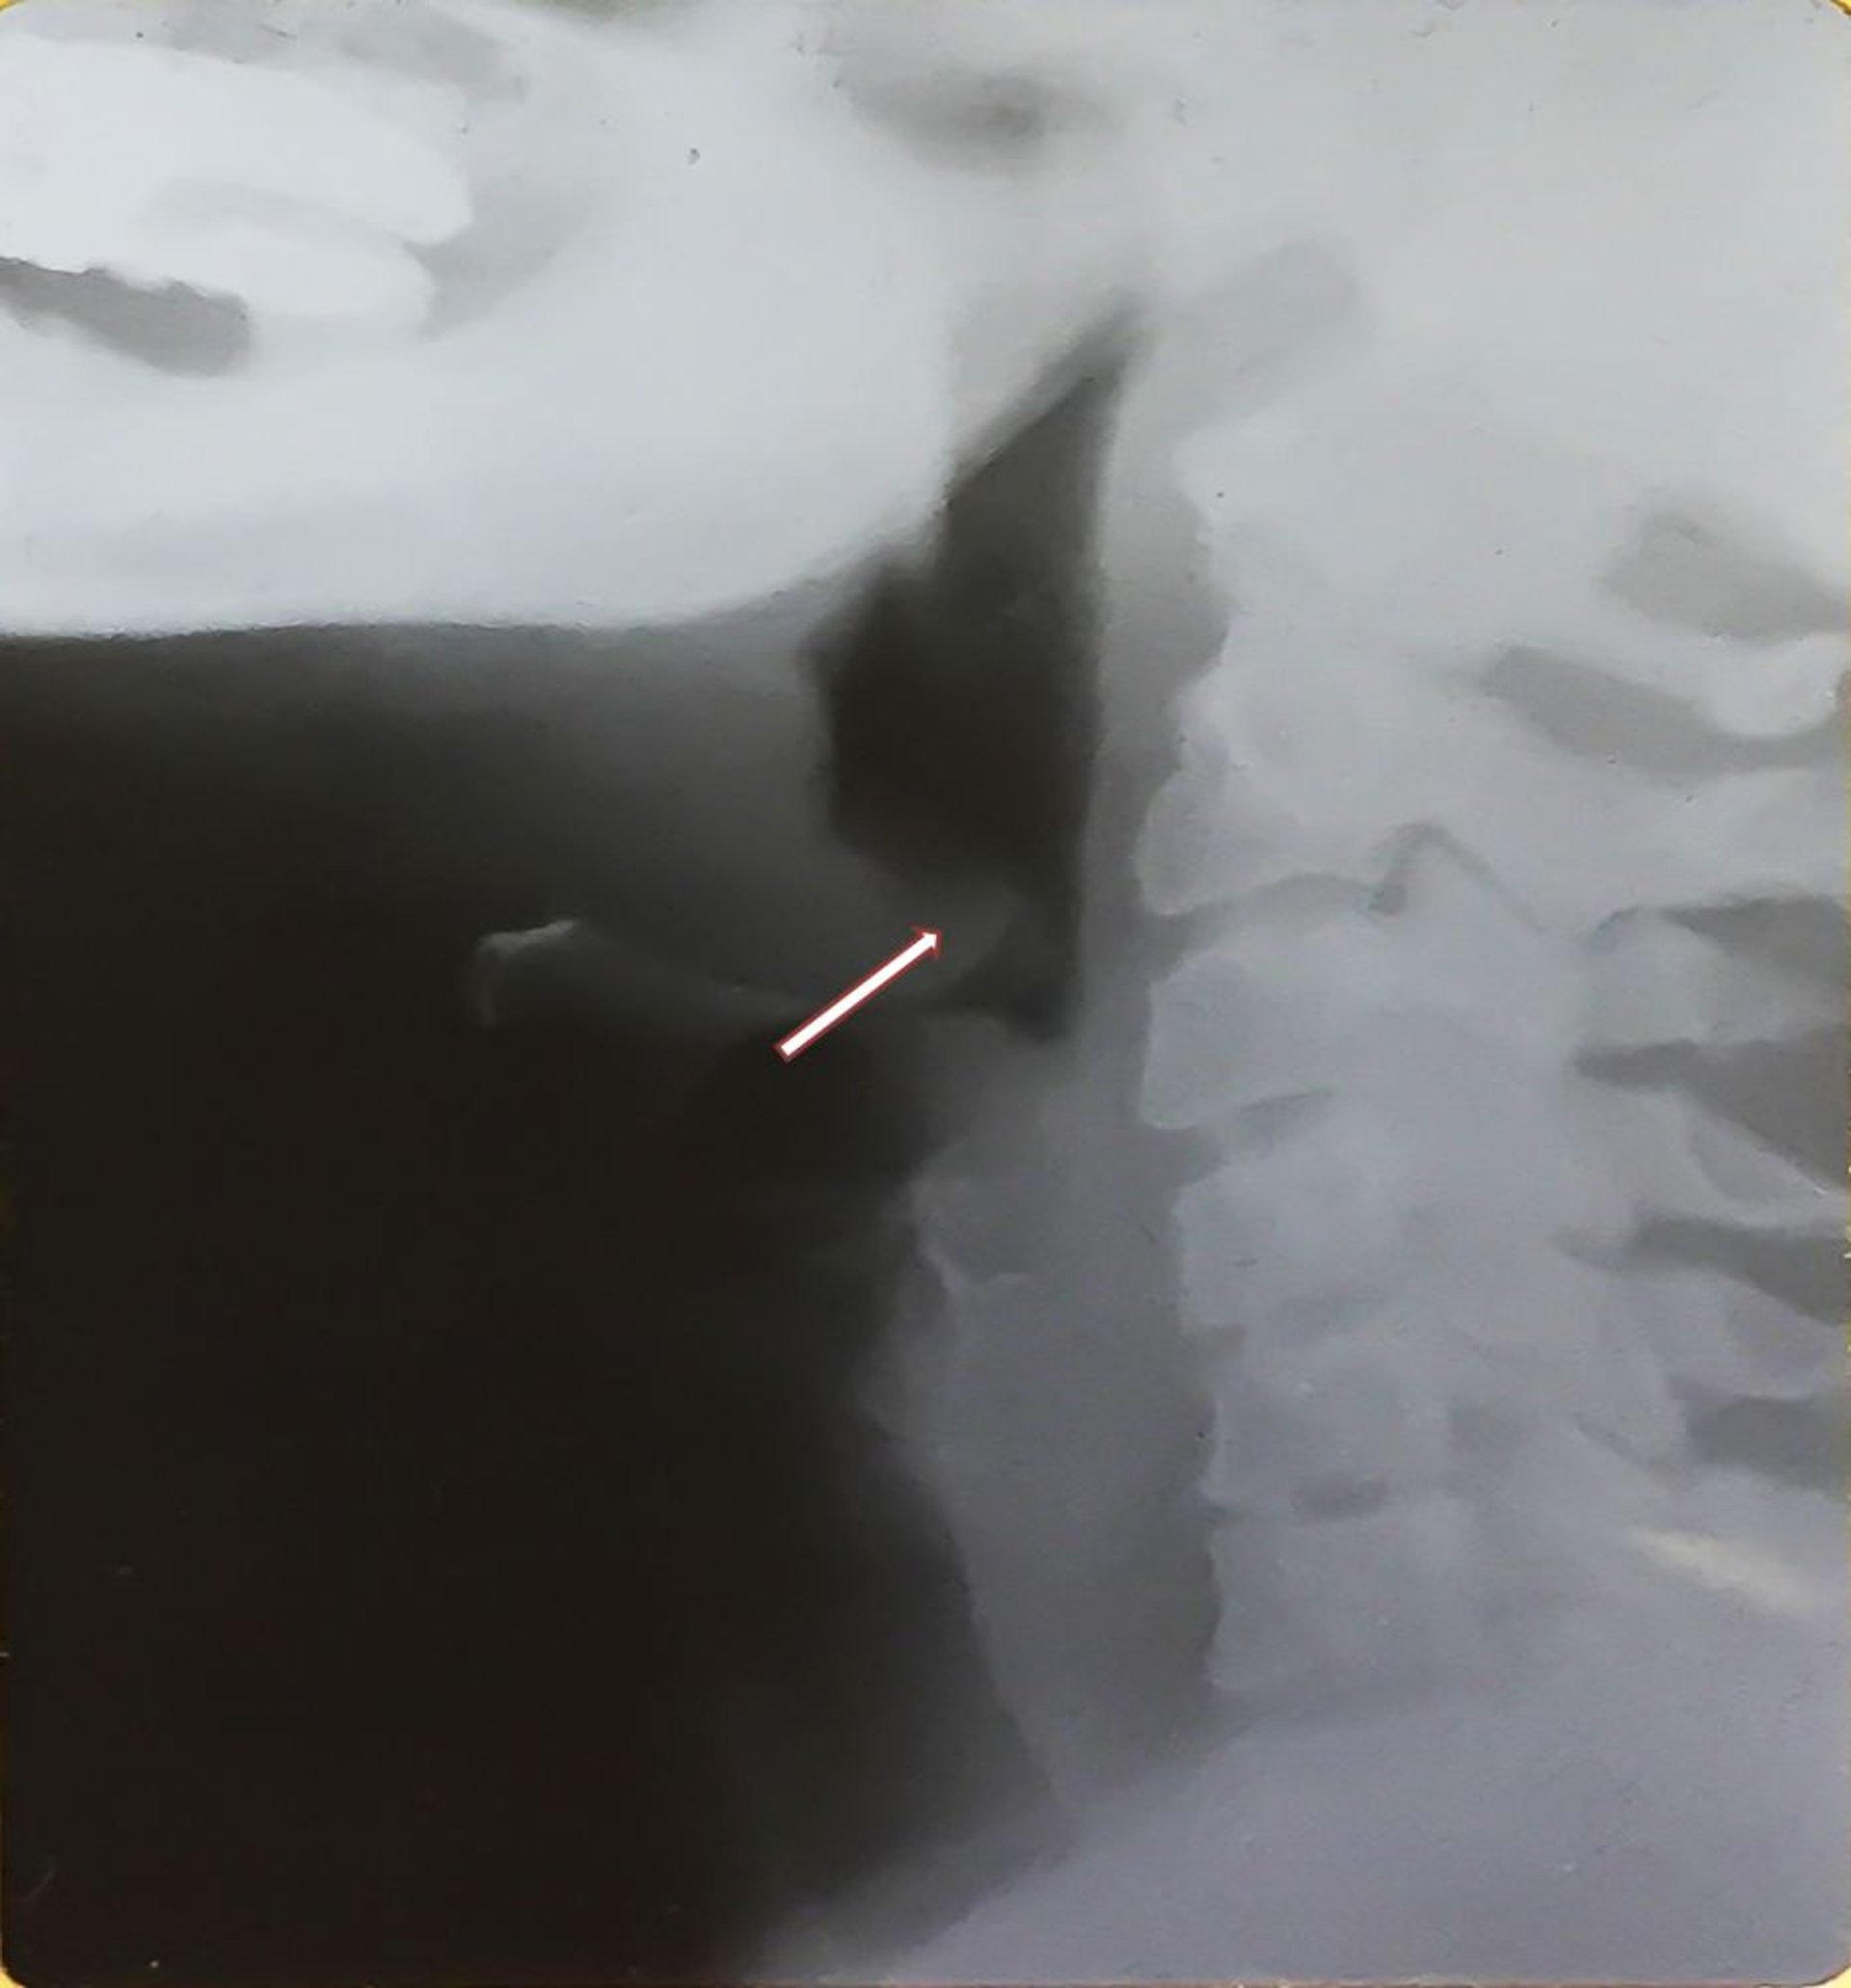

Epiglotitis (adulto)

Esta radiografía muestra el aumento de tamaño de la epiglotis (signo del pulgar—véase la flecha) característico de la epiglotitis y la distensión de la hipofaringe. Tenga en cuenta la epiglotis engrosada co desplazamiento posterior.

Image provided by Clarence T. Sasaki, MD.